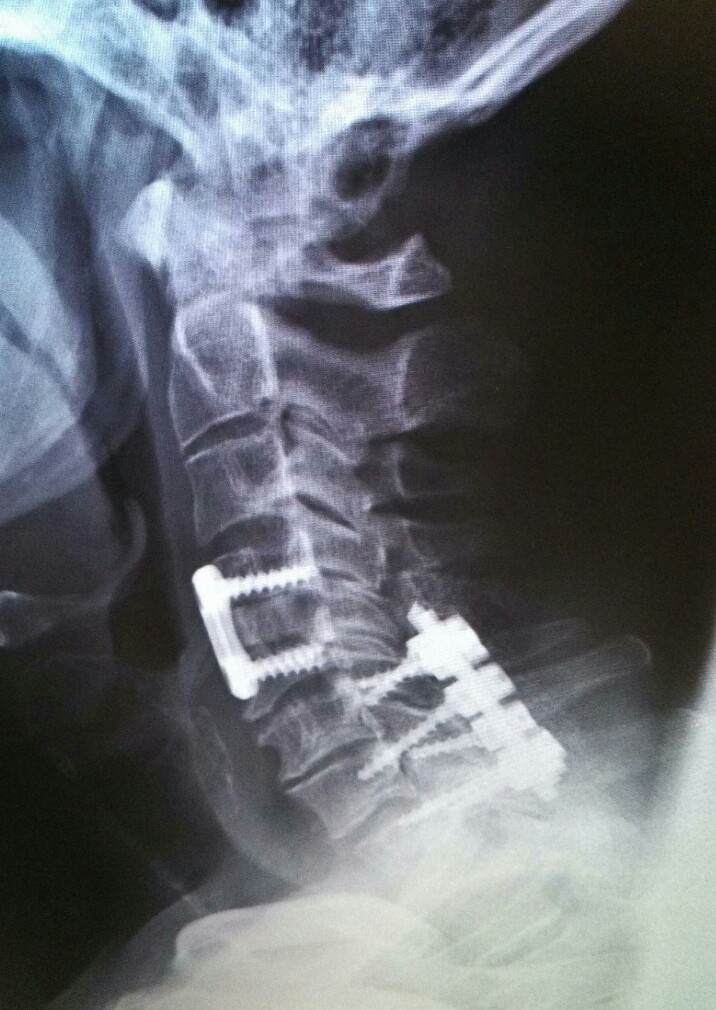

His surgery lasted over seven hours, partly because the surgical team constructed a special table to “flip” him over once the first part of the operation – inserting a plate with four screws through the front of his neck, was completed, so six more screws and four rods could be attached through the back of his neck/nape area, and he had to be painstakingly positioned because of the precariousness of his fractures shifting.